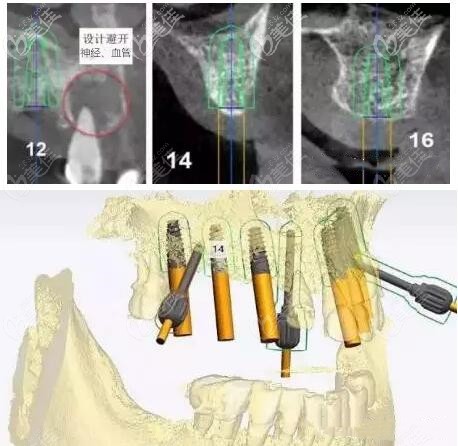

种植牙方案:即刻负重——由于上颌的牙槽骨条件较差,并且有较多的拔牙窝。所以,做即拔即种、即刻修复种植牙;利用3D数字化导板技术,避开牙神经、血管,找到合适的种植位点。

这样种植初期的稳定性才能更好,并实现即刻负重的效果。

拔除残牙→安装3D数字化种植牙导板→对照3D导板在牙槽骨上植入种植体→完成种植手术→戴临时牙冠。